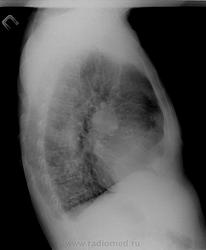

Случай 2.  М, 79 лет. ИБС, ГБ, обостение бронхита. Сейчас жалобы на подъем температуры до 38,4 кашель со слизисто-гнойной мокротой. Что скажете на счет него? Мне не нравится "мазня" с обеих сторон в нижних отделах, больше слева, правый корень и тень справа. Онкология может. Снимки на сегодня:

Снимки его за 7.6.13: Та же "мазня" слева

По второму - пневмонию в S6 справа пишем (онко - в уме). Рентген контроль после противовоспалительного лечения.

№2. Надо онко исключать.

А слева мазня и раньше была, и она не прогрессирует. Условия съёмки разные. Я расцениваю  эту картину, как остаточные явления ранее перенесенной пневмонии в S 9 слева.

Во втором случае расширенные, но в целом структурные корни, на боковом снимке кругление в корнях скорее всего за счет расширенной легочной артерии, инфильтраты в легких - в целом укладывается в картину застоя, после лечения можно посмотреть динамику в легких